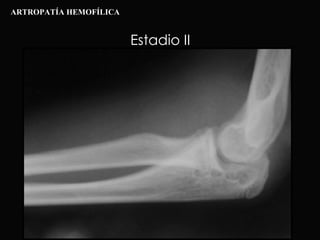

Estadio II ARTROPATÍA HEMOFÍLICA

Estadio III ARTROPATÍA HEMOFÍLICA